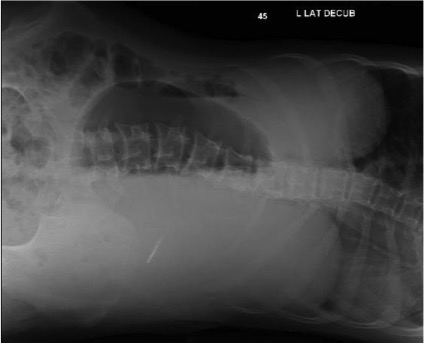

Figure 3. Abdominal radiograph, left lateral decubitus view, showing marked distension and lumbar scoliosis.